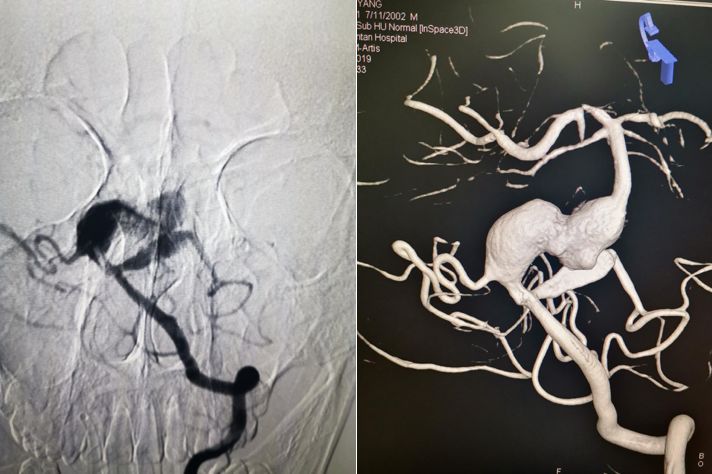

术后造影显示PED完全覆盖动脉瘤,载瘤动脉通畅。术后DynaCT 显示支架位置及打开良好。

术前右椎动脉造影显示:基底动脉中下段巨大夹层动脉瘤存在,PED支架向下移位脱落至基底动脉下段。

术前右椎造影:

术前右椎动脉路途下显示PED 支架向下回缩,支架近心端回缩不明显。远心端至动脉瘤下。箭头所示为支架远端脱落至动脉瘤内的位置。

PED支架顺利释放,与原支架顺利桥接重叠。术后即刻造影显示PED位置满意,动脉瘤内可见造影剂滞留。

DynaCT显示两枚支架形态良好。